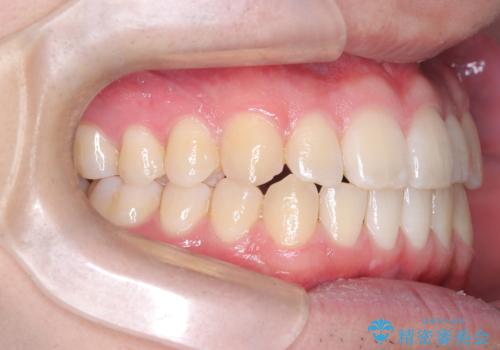

- 八重歯が気になるとのことでご来院されました。お口の中を確認すると、上の前歯がスペース不足で押し出され、少し前に出ている状態でした。抜歯せずに整えるため、奥歯を少しずつ後ろに動かしながら(遠心移動)、歯と歯の間をわずかに削るIPRを行ってスペースを作ることにしました。また、上下の噛み合わせを整えるために2級ゴム(エラスティック)を使用する方針を立てました。

マウスピースを段階的に交換しながら、奥歯を少しずつ後ろへ動かし、八重歯がきれいに並ぶよう調整しました。前歯の突出感を抑えるためにIPRを行い、スムーズに配列。さらに、2級ゴムを活用して噛み合わせも改善しました。治療後は、自然な歯並びになり、笑顔に自信が持てるようになったと喜んでいただきました。